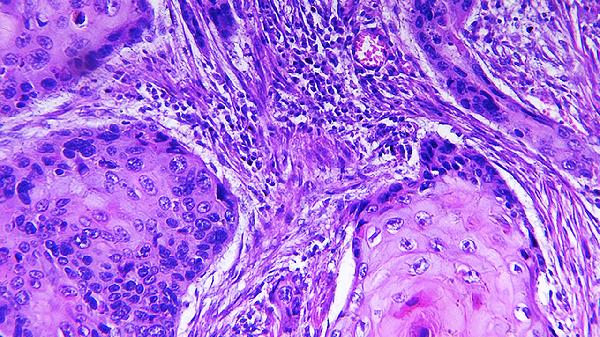

4、运动神经元

肌萎缩侧索硬化症选择性损害上下运动神经元,引起进行性肌无力和萎缩。利鲁唑片可延缓病情进展,需结合呼吸支持和营养管理。疾病晚期可能出现吞咽困难和呼吸肌麻痹。